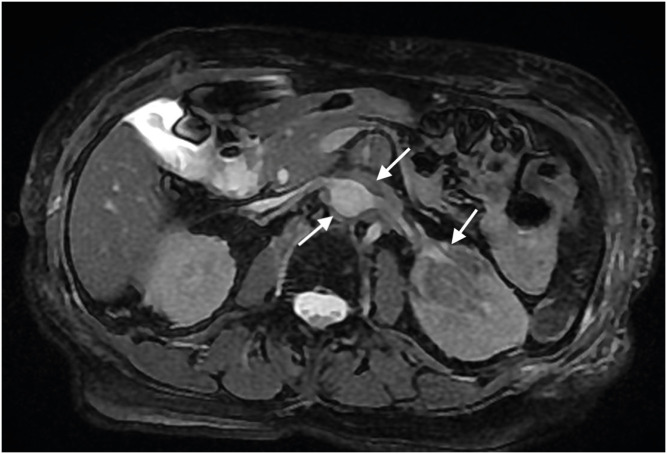

Erdheim-Chester disease (ECD) is a rare multisystem disorder characterized by mitogen-activated protein kinase (MAPK) pathway mutations. Herein, we present a unique case of ECD in a 79-year-old female with predominant breast nodules. Comprehensive imaging and histopathological evaluations confirmed the diagnosis. Mammography and ultrasonography revealed multiple hyperdense circumscribed nodules with coalescing masses and blurred margins. Core biopsy revealed infiltrating foamy cluster of differentiation (CD) 68+ and CD1a+ histiocytes. Because the tumor was negative for the BRAF V600E mutation, treatment with interferon-α was initiated. This case highlights the diagnostic challenges associated with ECD, the rarity of breast involvement, and the importance of considering ECD in the differential diagnosis of atypical breast lesions. Comprehensive imaging, histopathology, and genetic testing are essential for accurate diagnosis and treatment decision-making in ECD. Further research and awareness are required to improve recognition and management of this rare disease.